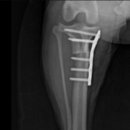

• 24시 에피소드 동물 메디컬 센터 | 만촌동 동물병원 강아지 요골·척골 골절 수술 후기 [24시에피소드동물메디컬센터]

만촌동 동물병원 강아지 요골·척골 골절 수술 후기 [24시에피소드동물메디컬센터] 만촌동 동물병원 ​ 안녕하세요. ​ 풍부한 경험과 따듯한 진료를 바탕으로, 반려동물의 건강하고 행복한 하루하루를 함께 만들어 가는 만촌동 동물병원 24시에피소드동물메디컬센터 입니다. 24시에피소드동물메디컬센터 대구광역시 동구...

에피소드동물메디컬센터(2025-06-26 12:41:00)